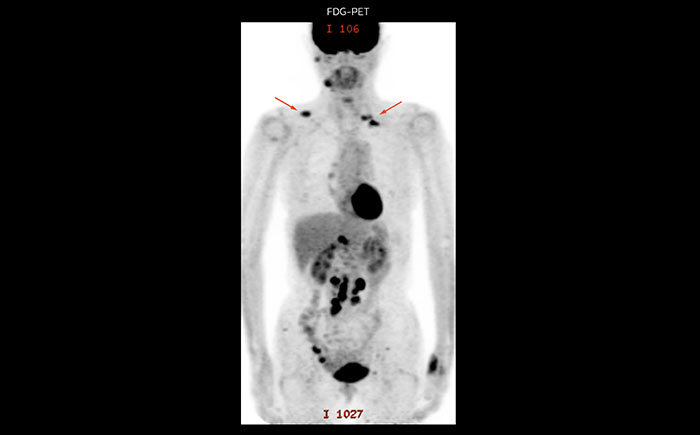

A 61-year-old female with a malignant lymphoma underwent an MRI exam with whole body diffusion weighted imaging (DWIBS) as well as PET. On the images shown, the resolution of DWIBS is better than PET, which allows visualization of the small pelvic lesions and almost no distortion is seen in the neck area.

Prodiva MRI whole body DWI lymphoma, Seirei Mikatahara

Prodiva MRI whole body FDG-PET, Seirei Mikatahara